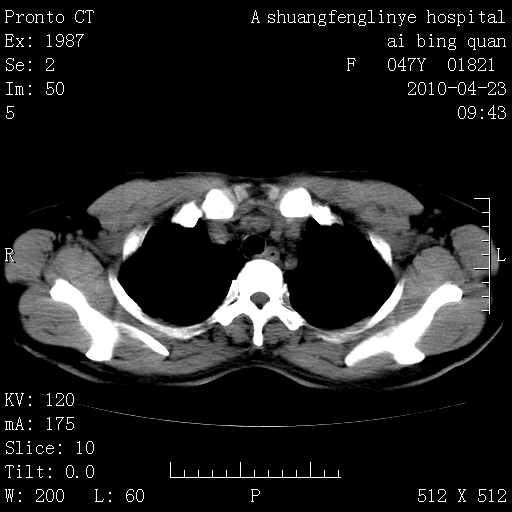

标题: CT25944:胸痛、气短、前几日高烧!肺Ca?请会诊! [打印本页]

标题: CT25944:胸痛、气短、前几日高烧!肺Ca?请会诊!

kaolv 周围型肺癌并同肺转移

双肺多发结节,考虑转移瘤,肺癌肺转移不除外

周围型肺癌并肺转移

左侧乳腺低密度灶

双肺多发结节,部分密度较高,最大结节边缘光滑。临床有“胸痛、气短、前几日高烧”病史。首选考虑:右肺感染性病变!建议积极消炎后复查!